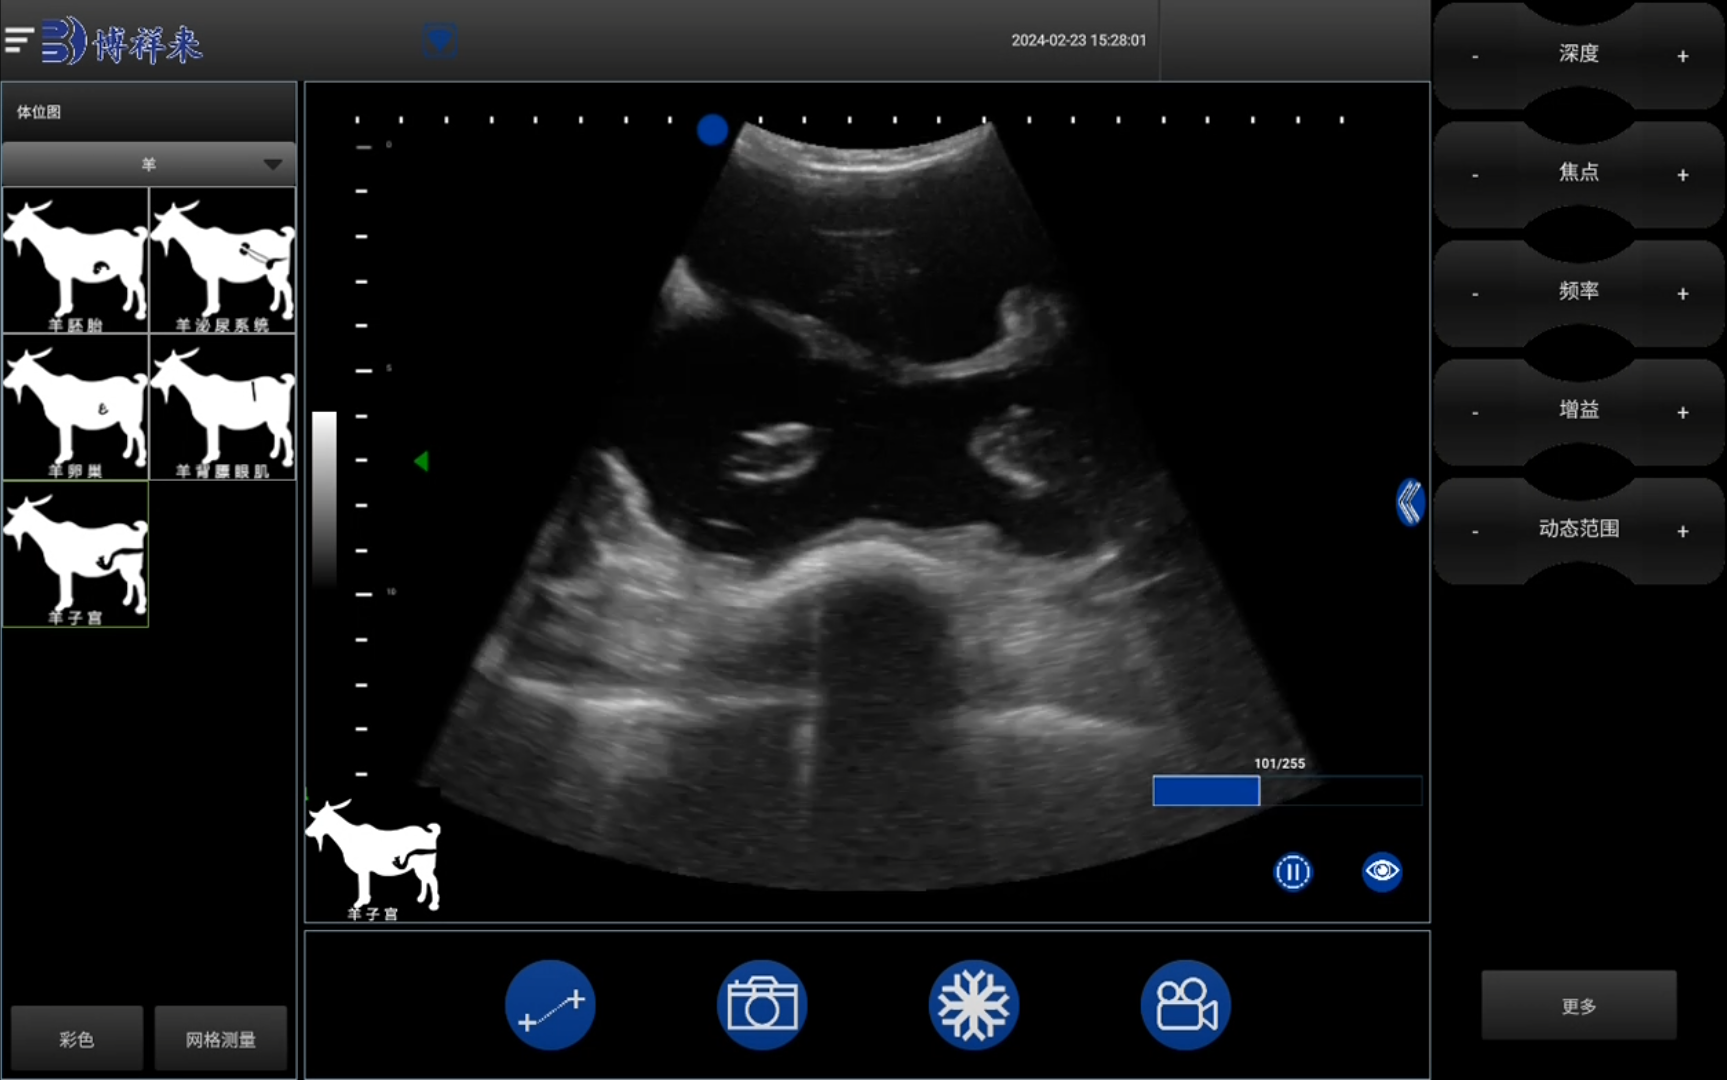

在现代畜牧业中,母羊的繁殖效率直接影响养殖场的经济效益。使用羊用B超进行双胎检测,不仅能提高母羊管理的科学性,还能帮助养殖户实现精细化管理,提升养殖收益。

羊用B超多胎检测仪

1. 精准检测。提升繁殖效率羊用B超能快速识别母羊怀孕情况,包括单胎、多胎甚至空怀。这种精确性为后续的母羊饲养提供了科学依据,有助于合理分配资源,提高繁殖效率。

• 精准检测技术:快速识别母羊双胎、单胎或空怀情况;